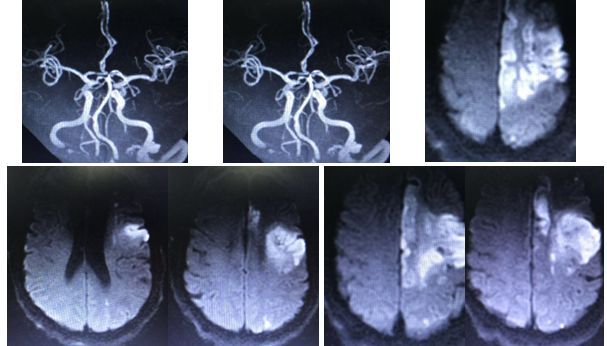

16:00:患者查颅脑磁共振

16:10:左侧额叶、顶叶、侧脑室旁多发急性脑梗死;多发缺血、梗死、软化灶;

左侧颈内动脉闭塞,具体原因不详,狭窄?夹层?

17:20颅脑CT排除出血

术后24小时复查,比入院后症状加重前稍加重

术后查体:BP 169/70mmHg,神志尚清,精神差,自动睁眼,能发音,左侧肢体可自主活动,右侧上肢刺痛反应,右侧下肢刺痛屈曲,右侧Babinski征(+),NIHSS评分9分。

住院12天,NIHSS评2分出院。